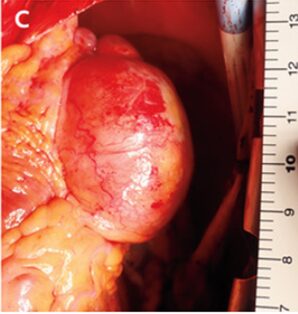

冠動脈CTにて左冠動脈から最大径45mmの動脈瘤が明らかとなった。

「巨大冠動脈瘤」と診断。動脈瘤の結紮縫合、瘻孔閉鎖術を含む心臓手術が行われた。